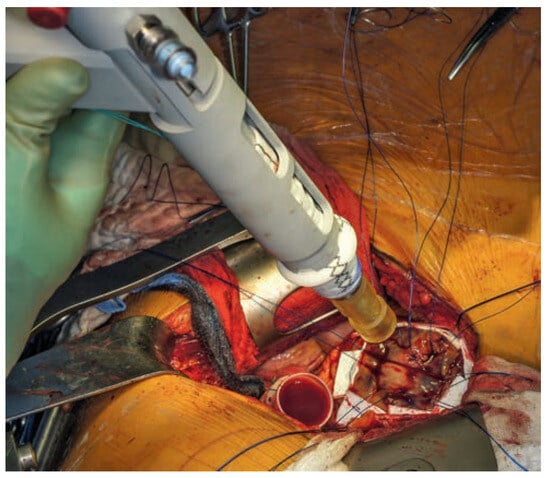

Case report A 22-year-old male experienced a presyncopal spell while studying for a university examination [...]